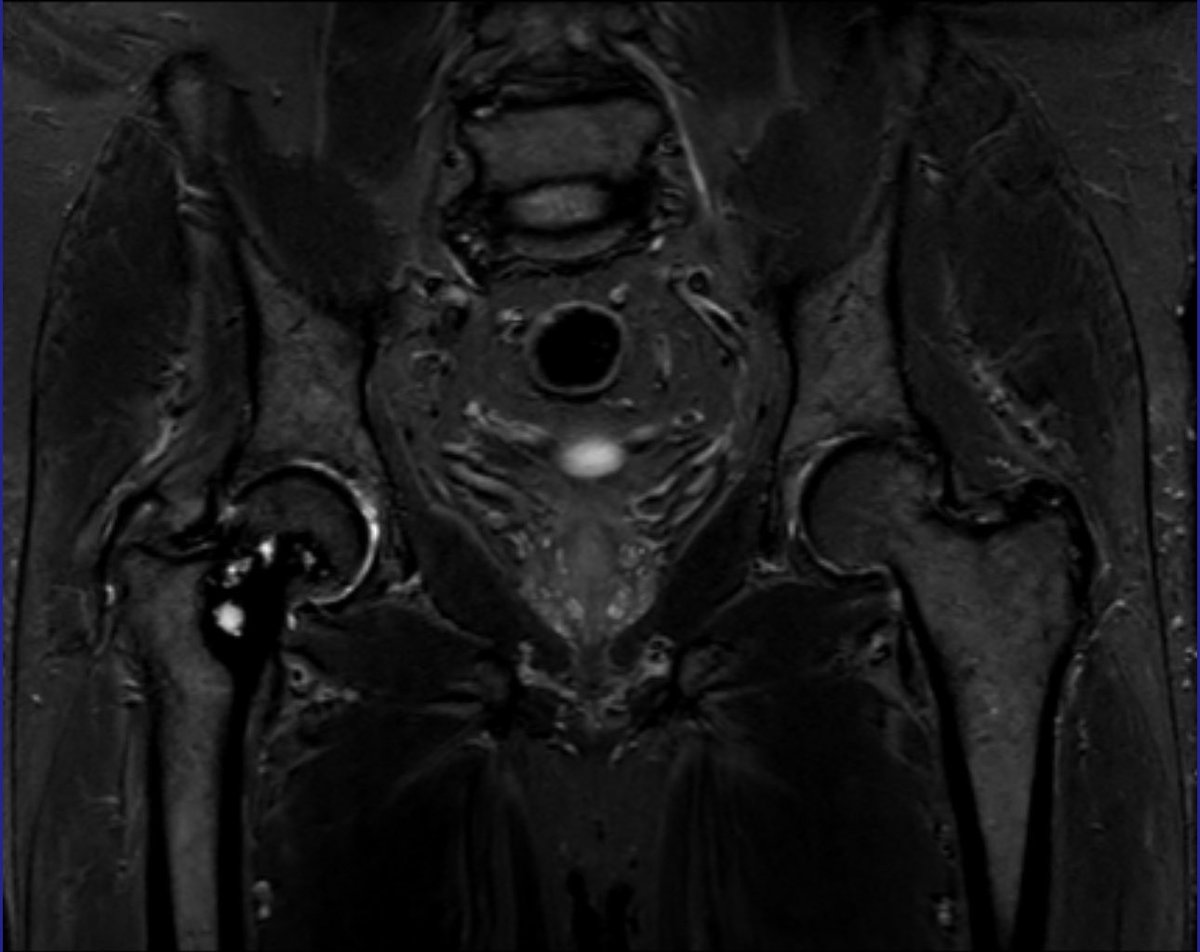

Consent ✅ Right hip pain & stiffness Both hip joints show OA changes - but R more advanced than L Why?

🕵️♂️ Dr. Murphey’s X-Files has arrived at Skeletal Radiology! 📂 Case #001 is now live. 👉 What’s the most likely diagnosis? 💡 Share your thoughts and come back to check the answer! Because, in the end, the truth is in the images. #SkeletalRadiology